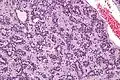

| Micrograph of an adenomyoepithelioma. H&E stain. | |

An adenomyoepithelioma of the breast is a rare tumour in the breast composed of glandular elements (adeno-) and myoepithelial cells. It is usually benign;[1] however, there are reports of malignant behaviour.[2]

The histomorphologic appearance can mimic invasive ductal carcinoma, the most common type of invasive breast cancer.